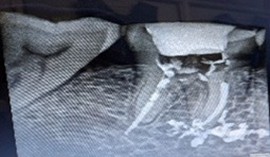

A 55-year-old woman presented to our department with a ten-day history of unrelenting pain in the upper right posterior region. Her prior medications provided no relief. Clinical examination of tooth 15 revealed mild vestibular swelling beneath a metal-free crown. Periapical radiography confirmed a large radiolucent area consistent with a periapical abscess. An earlier attempt at access had been made, with canals negotiated and prepared, but treatment remained incomplete.

We immediately initiated root canal therapy. Once the gingival swelling subsided, Metapex was placed as an intracanal medicament. The patient experienced no inter-appointment discomfort, and serial radiographs over five months demonstrated complete resolution of the lesion with restoration of healthy periapical bone.

Figure 1: Pre operative IOPA revealing incomplete root canal treatment with crown placement wrt 15.

Figure 1: Pre operative IOPA revealing incomplete root canal treatment with crown placement wrt 15. Figure 2: Root canal initiated through crown and metapex placed.

Figure 2: Root canal initiated through crown and metapex placed. Figure 3: Post operative IOPA after 2 months reveals marked reduction in the lesion.

Figure 3: Post operative IOPA after 2 months reveals marked reduction in the lesion. Figure 4: Post op IOPA after 5months reveals complete healing of periapical lesion, crown removal done, root canal master cone IOPA confirms.

Figure 4: Post op IOPA after 5months reveals complete healing of periapical lesion, crown removal done, root canal master cone IOPA confirms. Figure 5: Post obturation IOPA.

Figure 5: Post obturation IOPA.